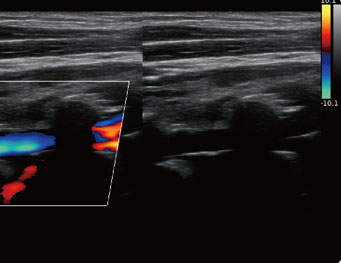

Chison Qbit 5 Color Doppler Ultrasound Machine

Q Flow:

- This Adaptive Color Detection Technology Can Automatically Adjust The Assessment Of Color Signal And Noise According To Different Tissues.

- As A Result, The Color Sensitivity Of Low – low-velocity flow Is Significantly Enhanced.